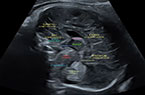

Grossesse de 11 SA - éléments anatomiques du sac gestationnel et du foetus - Iamges cliniques Grossesse de 11 SA - éléments anatomiques du sac gestationnel et du foetus - Iamges cliniques Grossesse de 11 SA - éléments anatomiques du sac gestationnel et du foetus - Iamges cliniques